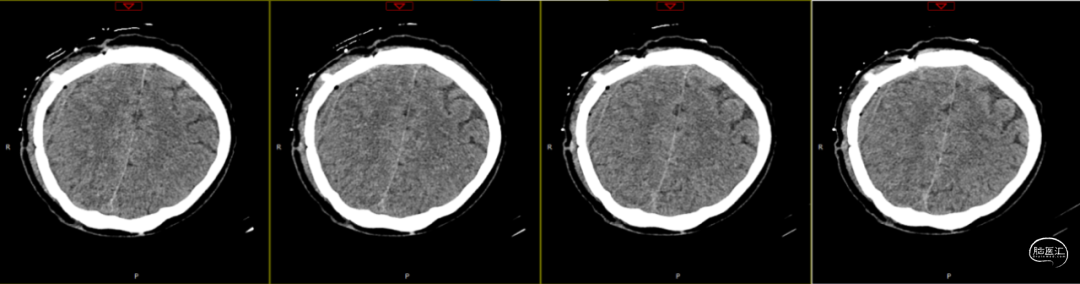

因患者局部头皮逐渐膨隆,且头皮疼痛,于术后89天再次入院。体查可触及头皮下异常物质存在,考虑头皮下积脓并硬膜外脓肿可能,患者无发热,血常规、C反应蛋白、降钙素原等感染指标均为在正常范围。

第1次术后88天,即第2次入院前1天复查(如上图),经反复沟通病情,病人及家属仍拒绝去除骨瓣清创手术,但同意进行手术清创。术中见右侧额部皮下炎性肉芽组织增生,伴有少量分泌物流出,骨瓣下见乳白色脓性分泌物,未闻及明显异味,收集脓性液体送细菌培养、涂片检查,局部硬膜增厚,较多炎性增生组织于局部硬脑膜黏连紧密,缓慢刮除局部异常增生组织后,低功率双极电凝行硬脑膜止血,骨瓣可见右侧额部外板局部被侵蚀,清理表面异物后,使用双氧水浸泡冲洗,并浸入碘伏液中消毒;彻底清除硬膜外、骨缘及右侧额部皮下增生异常组织,额顶部愈合不良刀口予以局部清创,反复使用双氧水及稀释后碘伏溶液冲洗创面,更换钛板及钛钉,还纳骨瓣并固定,皮下留置负压引流管1根,缝合逐层。术后使用万古霉素静脉抗炎治疗,留取术中脓性分泌物进行细菌培养及涂片检查(培养及检验均呈阴性)。

第2次术后第1天复查颅脑CT资料(第1次术后92天)(如上图)。